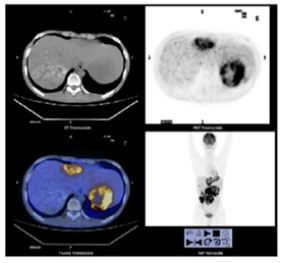

A 21-year-old man presented with a 11-month history of abdominal distension, abdominal pain and occasional vomiting. Positron emission tomography–computed tomography (PET-CT) revealed a 12.9 × 15.1 cm, well-encapsulated, low-density and heterogeneous enhanced lesions with necrosis and calcification in the right lobe of the liver (Figure 1). Furthermore, multiple low-density nodules and the largest one was about 16.2 × 6.9 cm were also detected in the left lobe of the liver. No mass lesions were detected in other organs, including the thyroid gland, kidneys, breast, prostate and cervical lymph nodes. Radiological diagnosis were primary liver cancer with intrahepatic metastasis. Viral markers were non-reactive. Serum alpha fetoprotein (AFP) was 5.80 IU/ml (normal limit was < 5.5 IU/ML) and carbohydrate antigen 199 (CA199) was 81.89 U/ML (normal limit was < 27 U/ML). Thyroid function tests were normal. The patient underwent needle biopsy of the mass in the right lobe of liver, then received transcatheter arterial chemoembolization and protective liver treatment. At the final follow-up 8 months after the initial tumor puncture, the patient was alive without tumor development or new metastasis.

Figure 1: The volume of the liver is obviously increased. Multiple slightly low-density nodules and masses are seen in the liver. The density is uneven, with necrosis and calcification in some parts. The larger one is located in the right lobe of the liver, and the maximum cross-section size is about 12.9 cm × 15.1 cm.

PET showed increased partial radioactivity uptake at corresponding sites, with SUV max of about 12.7. Many calcifications in the tumor are showed and the metabolism of the lesion is different.